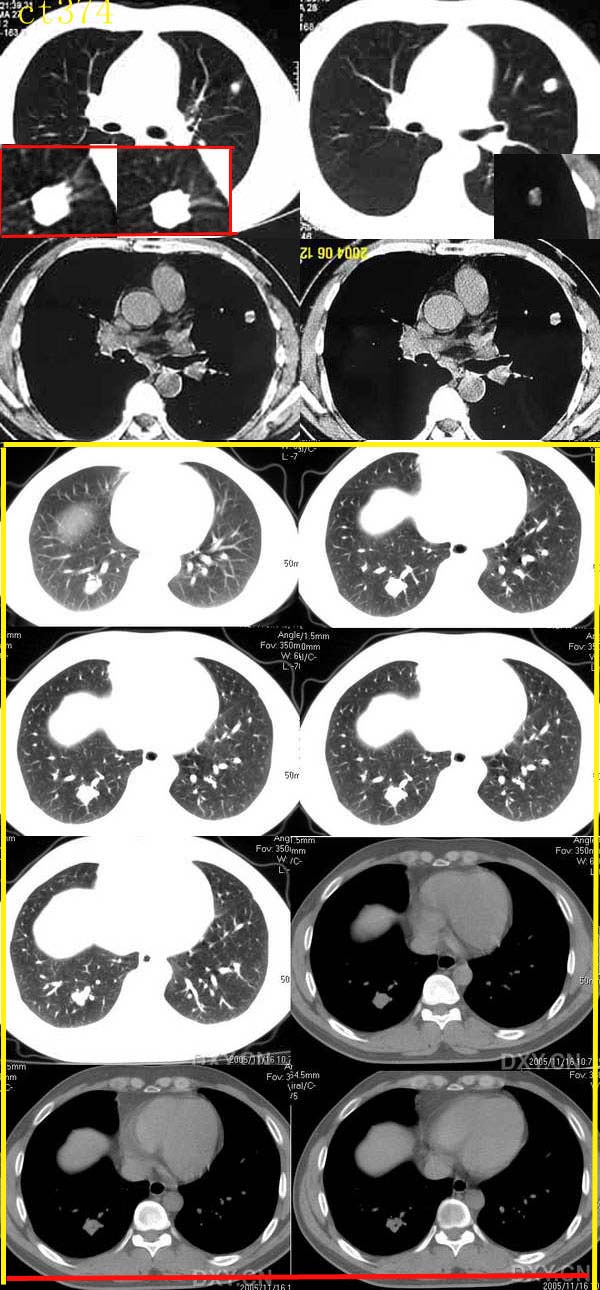

ct0374向医生提供:肺错构瘤。

男,47岁,无明显症状,体检时胸片发现左肺小结节影.

http://www.radida.com/radinet/read.php?tid=1069